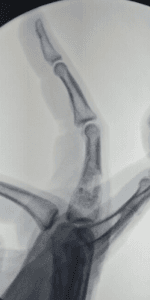

Homem, 23 anos, apresentando edema em região de sobre falange proximal de dedo anelar direito há seis meses, sem queixa de dor.

Qual é o diagnóstico mais provável?

DEncondroma